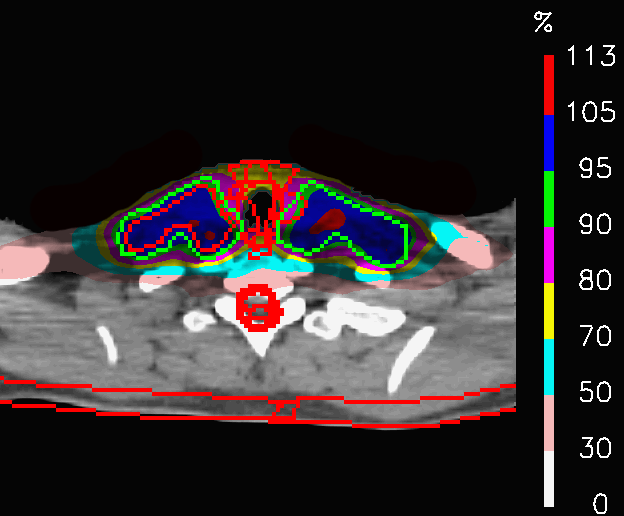

In PLAN-OL-2, a different field geometry has been investigated: the posterior fields are switched off at the level of the shoulders, the anterior ones at the level of the head and a fifth intracranial field is added (Fig.6). The goal was to achieve a better preservation of the OARs inside the head. The dose distributions (Fig.16) share a very similar coverage of the target volume, but they are characterized by substantial differences in the dose delivered to the OARs, as shown by Table 5. In fact, the huge improvements in the sparing of the chiasm, right lens (Fig.17a), left lens (17b), left inner ear and the spinal cord (considering in first place the decrease of 𝐃𝐦𝐚𝐱subscript𝐃𝐦𝐚𝐱\mathbf{D_{max}}) are followed by a significant increase of the peak dose inside the thyroid and the mean dose to the brainstem. In this case, PLAN-OL-2 is not necessarily superior to PLAN-NOM, but it is undeniable that the OL penalization has allowed the planner to test a scenario, that the simple enforcement of the dose constraints would not have provided.

Refer to caption

(a) PLAN-NOM

(b) PLAN-OL-1

Figure 14: Head and neck tumour: dose distributions of PLAN-NOM and PLAN-OL-1 at the level of the shoulders.

(a) Esophagus

(b) Spinal cord

Figure 16: Head and neck tumour: dose distributions of PLAN-NOM and PLAN-OL-2 at the level of the head.